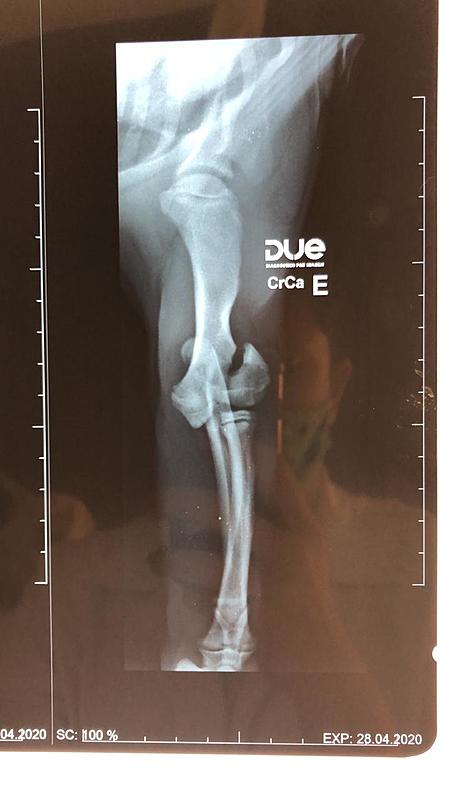

Pessoal o Theo (meu buldogue francês) sofreu uma queda e quebrou sua patinha. Devido a crise do corona vírus e por estarmos em quarentena, estou sem trabalhar, o salão esta fechado. Sou comissionado. Peço ajuda de todos que puderem c ver tudo

Pessoal o Theo (meu buldogue francês) sofreu uma queda e quebrou sua patinha. Devido a crise do corona vírus e por estarmos em quarentena, estou sem trabalhar, o salão esta fechado. Sou comissionado. Peço ajuda de todos que puderem contribuir com qualquer valor. Meu muito obrigado desde já. Glauber Marcelino